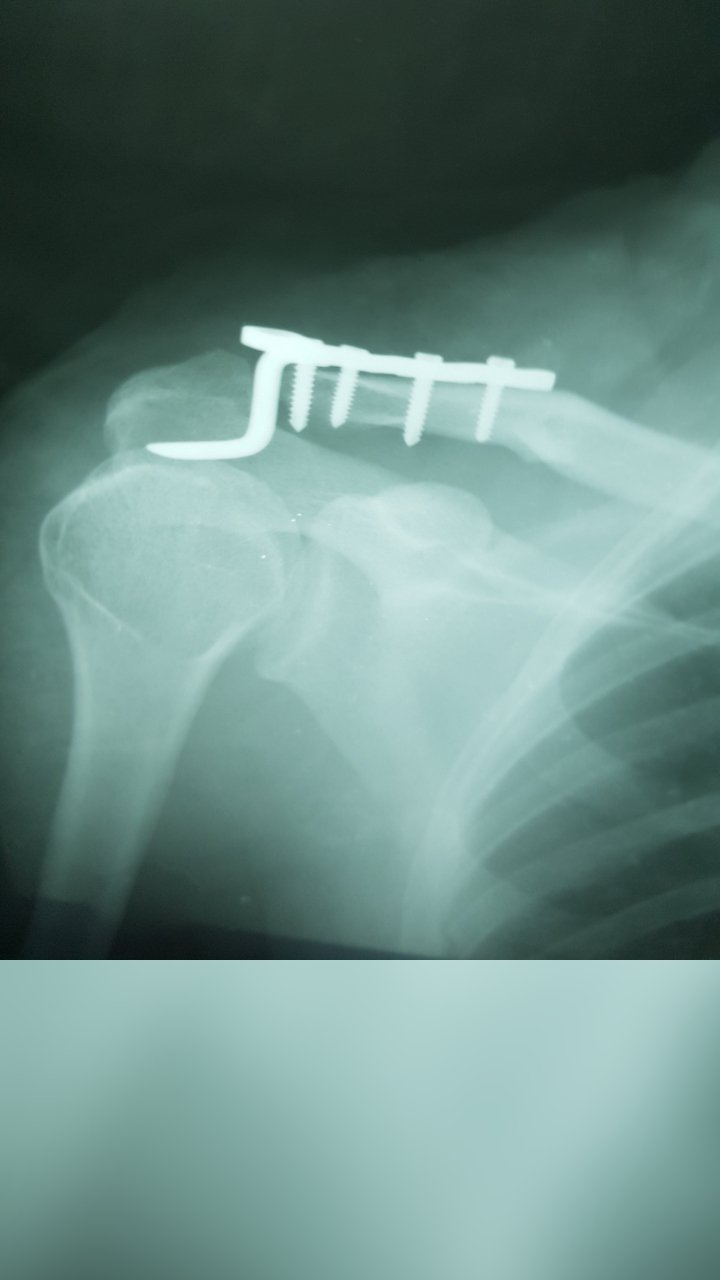

LATERAL CLAVICLE FRACTURE SURGERY

ACROMIOCLAVICULAR JOINT SURGERY